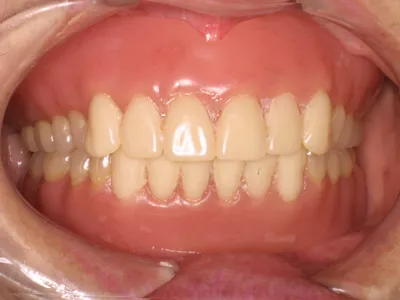

| 自費ブリッジ |

保険のブリッジ

|

通常のブリッジでは 正面から金属が見えてしまいますが ピンレッジでは見えません ■長所 ・金属が見えない ■短所 ・前後の歯を裏だけ削る ・前後の歯が健全な場合のみ可能 ・高い |